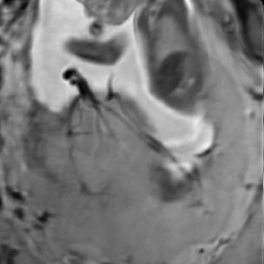

During image acquisition the fetus is not sedated and moves freely as well as the mother breathes normally. As a result, movements are likely to corrupt the scans, hiding pathology and causing overlap between different anatomical regions. In order to limit these artifacts, fast scanning sequences such as ssFSE [10] allow for the rapid acquisition of single slices at high in-plane resolution in a large field of view and good tissue contrast of the uterus. However, when acquiring a 3D volume through a stack of slices, inter-slice artifacts in the out-of-plane views are highly likely. Consequently, this restricts reliable diagnostics to individual slices in the current clinical practice. Fig. 1 depicts a typical example of motion related artifacts in a fetal single-shot fast spin echo (ssFSE) scan. The observed motion (c.f. Fig. 1 b & c) is of unpredictable nature and consists of a combination of maternal respiration movements, fetal movements and bowel movements.

Reconstruction of Fetal Organs: Exemplary PVR and SVR reconstructions under motion introduced by kicking of the fetus are shown in Fig. 11. PVR reconstruction results show an improved visual appearance and less blurring in the region with severe motion artifacts (arrow). An example of a challenging clinical case with a kidney malformation in one of twin fetuses, is shown in Fig. 8. Our clinical partners confirmed that such complications are easier to examine and to quantify after PVR-based reconstruction.